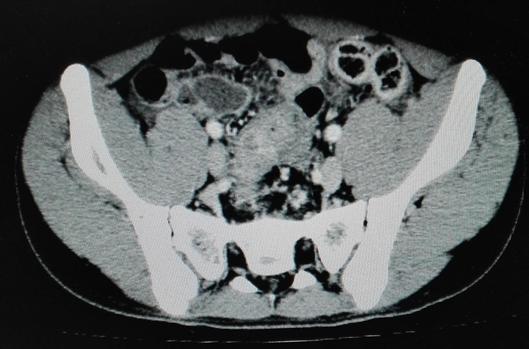

克唑替尼口服3日后,患儿腹部肿块逐渐缩小至4cm*3cm;口服第6天,腹部较前变软,未再排血便,神智较前转清,对答切题。体查:三凹征(-)中下腹部包块3cm*3cm。口服克唑替尼后第12天,患儿无胸水流出,能自行进食,腹部肿块缩小至2cm*2cm,患儿出院。患儿不规律口服克唑替尼一个月后,自行停药。复查腹部CT:腹腔大网膜肿块,互相融合,最大约7.1cm*4.7cm,较初诊外院片缩小。

停口服药治疗后3个月